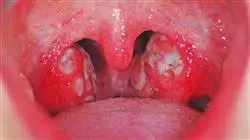

Esta capacitação é uma resposta a uma necessidade importante no campo da Infectologia. Hoje, esta necessidade responde, entre outras coisas, ao surgimento de certas doenças desconhecidas ou de pouca prática (zika, chikungunya, febres hemorrágicas, etc.), e outras que caíram no esquecimento ou são desconhecidas pelos farmacêuticos menos experientes, como difteria, sarampo, coqueluche, ou paralisia flácida associada ao vírus da vacina contra a poliomielite.